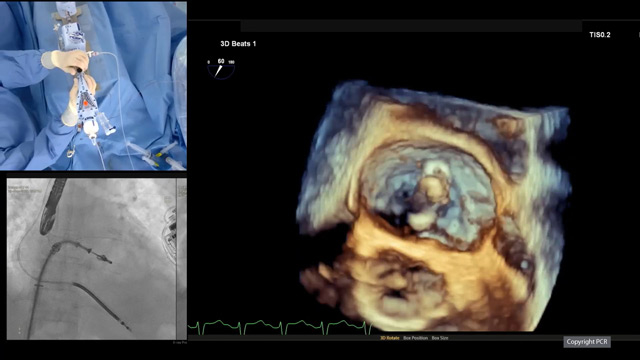

Mitral transcatheter edge-to-edge repair - LIVE Case

29 Sep 2025 – From PCR Gulf Valves 2025

This live educational session from Prince Sultan Cardiac Center in Riyadh offers an in-depth look at mitral transcatheter edge-to-edge repair (TEER) with MitraClip. Learn best practices for patient selection, imaging analysis, operator strategies, and witness a live case procedure to optimize clinical outcomes.

LIVE Educational Case from...